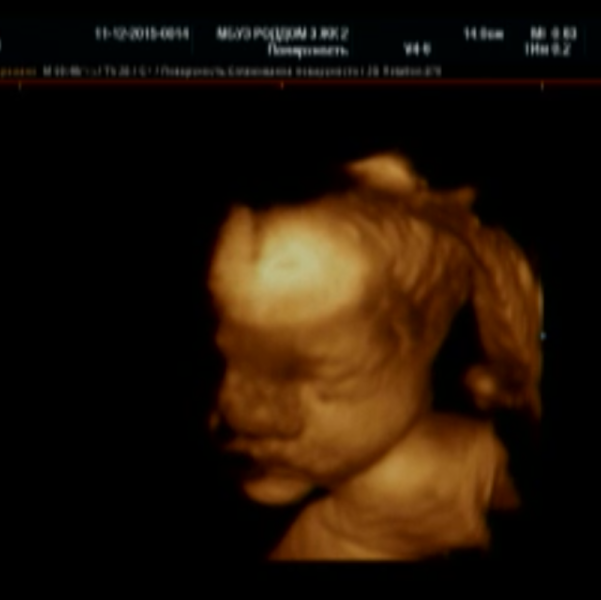

Солнышко моё, моя радость, мамочка ждёт тебя уже вот эти 9 прекрасных месяца.😊 Очень надеюсь, что увижу твоё чудное личико 7 февраля, в этот прекрасный день!😇 Я сделаю все, чтоб ты родилась здоровенькой и крепенькой!😄 Непременно жду встречи с тобой, очень хочу прижать тебя к себе, почувствовать твой нежный запах, обнять, поцеловать и не отпускать 😍😘